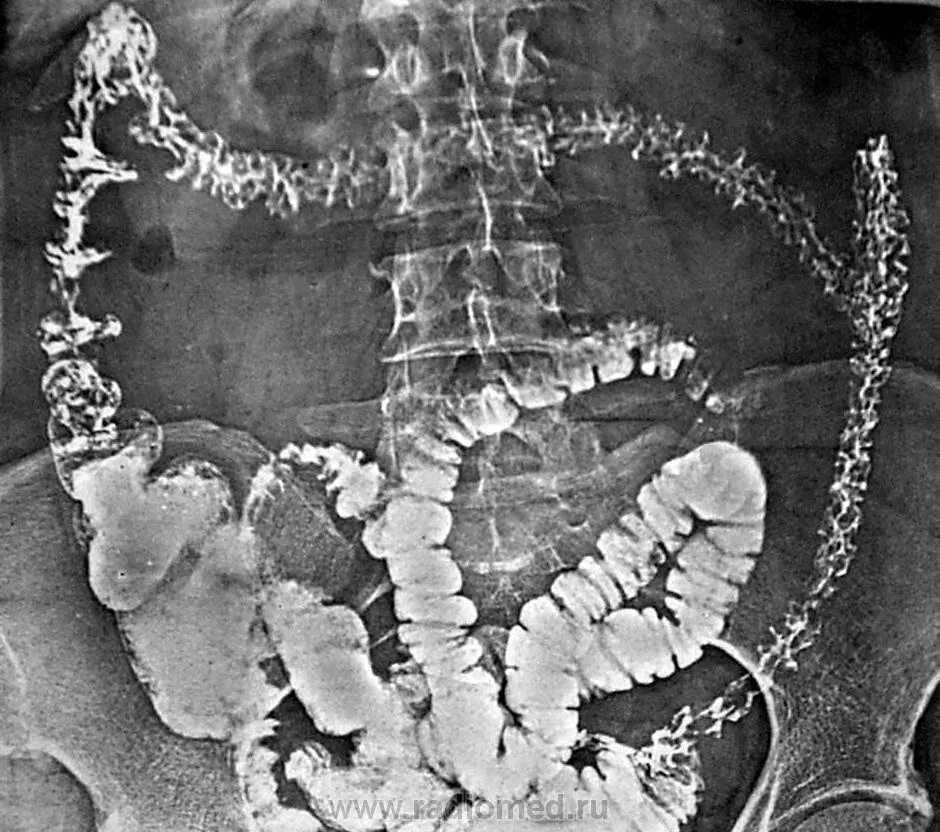

Ирригоскопия с двойным контрастированием